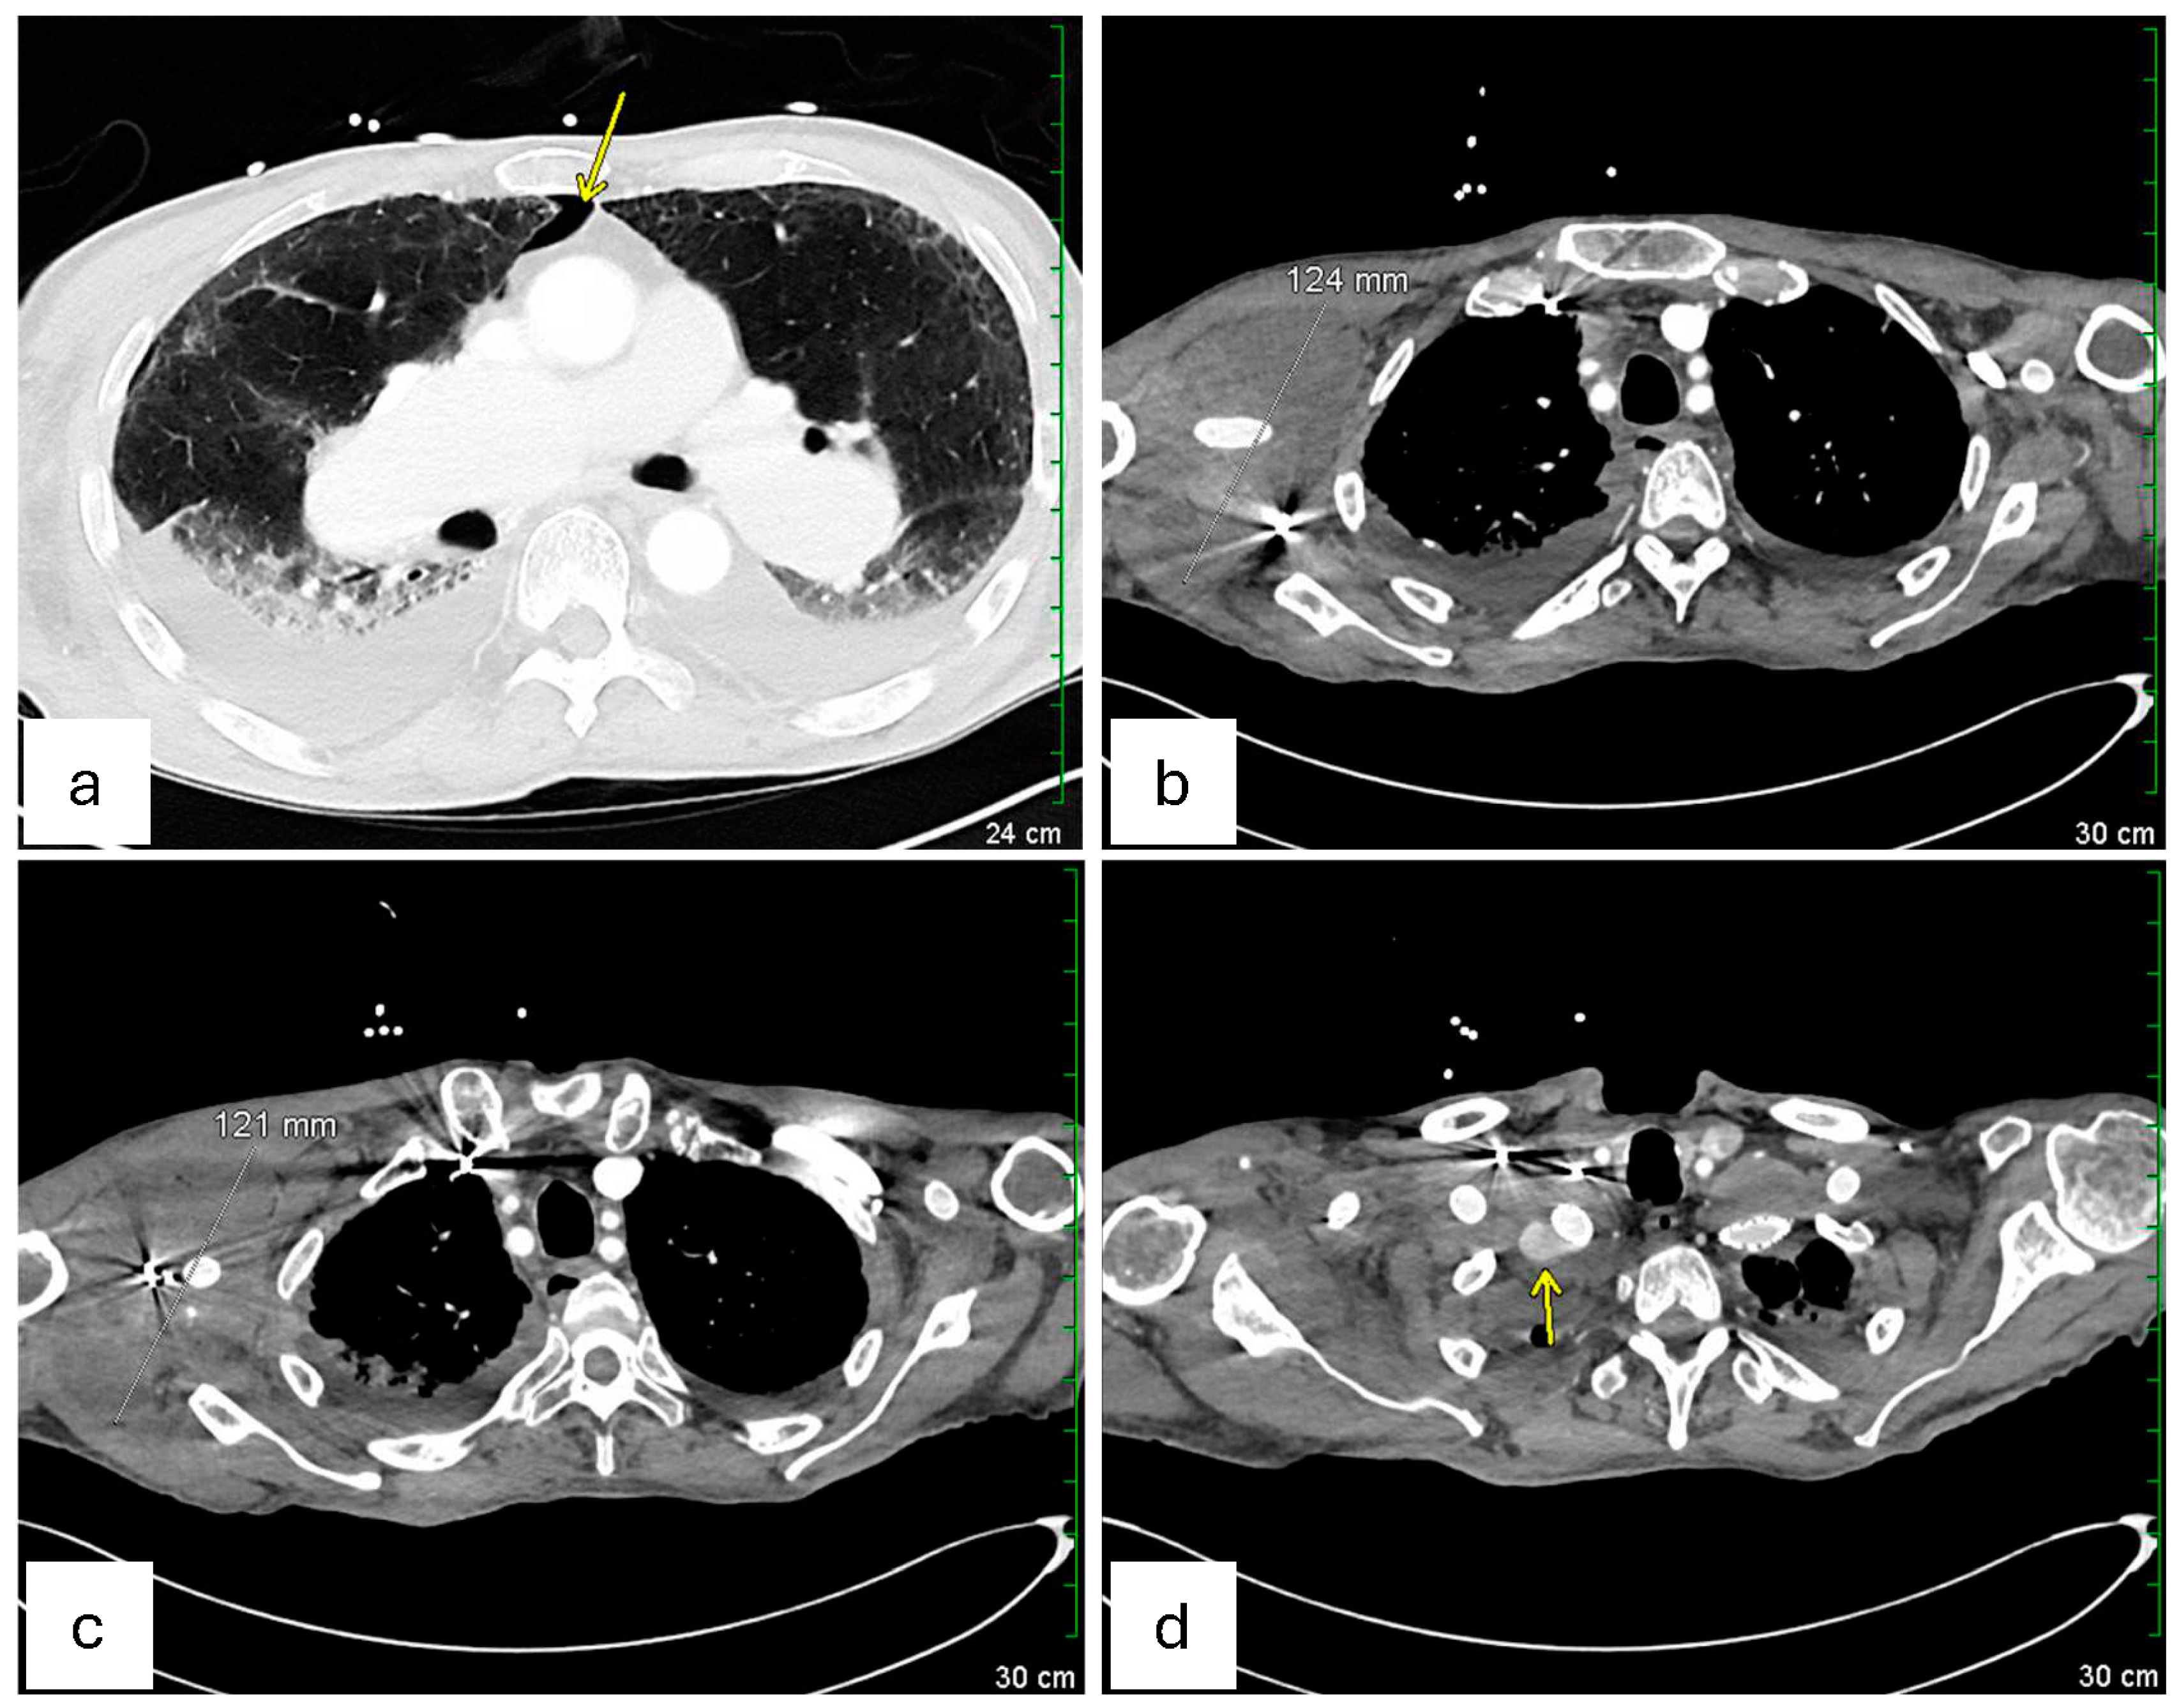

Given the symptomatic presentation and partial rupture of the right subclavian artery aneurysm, an emergent endovascular intervention was performed on the day of admission after obtaining informed consent. The procedure was performed under moderate sedation for 3 h. Vascular access was obtained via ultrasound-guided retrograde right common femoral artery access, and a pigtail catheter was advanced into the proximal ascending aorta for arch and thoracic aorta angiography. Selective catheterization of the right subclavian artery confirmed a large, contained rupture in the mid-subclavian segment, approximately 1 cm distal to the vertebral artery takeoff. Intravascular ultrasound (IVUS) was performed to delineate vessel dimensions and the aneurysm’s relation to the vertebral artery. The intervention involved embolization of multiple collateral branches (right transverse cervical, suprascapular, and internal mammary arteries) using Ruby coils to minimize endoleak risk. Subsequently, an 11 × 59 mm VBX stent (Flagstaff, AZ, USA) was deployed in the mid-subclavian artery with post-stent balloon angioplasty using a 12 × 40 mm balloon. A completion angiogram confirmed successful exclusion of the aneurysm without evidence of endoleak, with brisk antegrade flow into the vertebral artery and upper extremity vasculature. The procedure concluded with percutaneous closure of the right femoral artery using ProGlide Perclose. This procedure succeeded in restoring normal arterial flow and preventing further bleeding. Notably, pre-procedural IR imaging also identified a large left subclavian artery aneurysm, measured to be 56.4 mm * 54.2 mm in dimension, with a contained rupture at its mid-segment, approximately 1.5–2 cm distal to the vertebral artery origin (Figure 2c). The left-sided aneurysm was not well visualized on CTA of the right extremities but was confirmed on angiography.

Figure 2. Pre−procedural imaging studies demonstrate the bilateral subclavian artery aneurysms, their dimensions, and associated vascular pathology. (a) Axial CTA of the right upper extremity demonstrates a large diffuse soft tissue hematoma measuring 76.7 mm * 108 mm, with perivascular soft tissue thickening, without evidence for active extravasation at this time. The aneurysm is located in the mid−subclavian artery, just distal to the vertebral artery takeoff, corresponding to the site of prior stent graft placement. (b) Axial CTA of the right upper extremity reveals irregular morphology of the proximal right subclavian artery measuring 2.5 * 3.3 cm with surrounding thrombus at the right subclavian artery region, measuring 21.9 mm * 33.3 mm, likely indicating partial rupture or pseudoaneurysm. (c) Pre−procedural digital subtraction angiography (DSA) of the left upper extremity from the interventional radiology (IR) suite shows a left subclavian artery aneurysm measuring 56.4 mm * 54.2 mm at its widest diameter. The aneurysm is approximately 1.5−2 cm distal to the vertebral artery takeoff, with evidence of a contained rupture. (d) DSA of the aortic arch and left subclavian artery demonstrates the perfusion of the aneurysm and confirms the location of the pathology before planned intervention on day 1 of hospitalization.